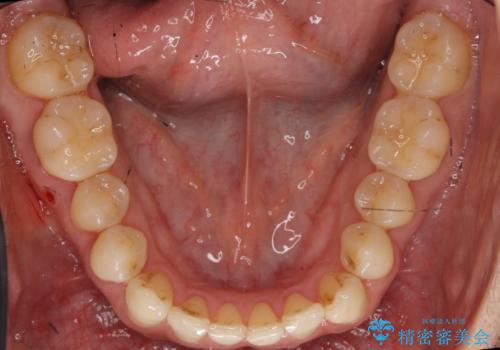

受け口 マウスピースで矯正治療 難易度:中

- 受け口を主訴に来院。

前歯の反対咬合でしたが、かみ合わせが、下顎が大きく前方にずれていました。

引っ込んでいる前歯の前方に下の犬歯が深く咬み込んでおり、また、奥歯のかみ合わせも受け口方向にずれ、骨格性の反対咬合も少々ありました。

上の前歯を前方に出すだけでは治療ができないため、ミニスクリューを用いて下の奥歯を後ろに送っています。

また、下の前歯を0.3mmずつIPRしています。

前歯の反対咬合にしては、難易度は中等度だと思います。

ちょっと前歯を外に出すだけでは治療は難しいです。

下の奥歯を後ろに送るにも、親知らずを抜いたスペース等がなければ難しいです。